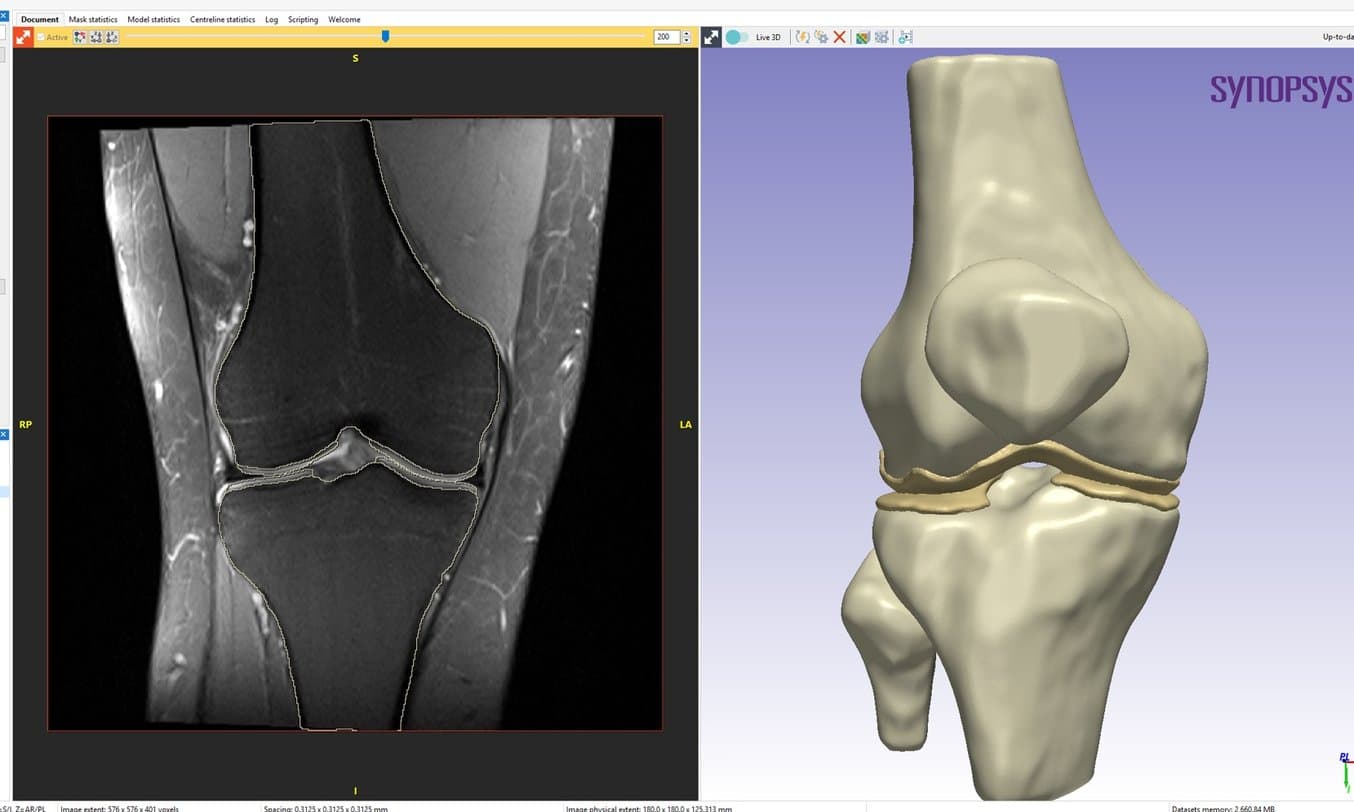

Three-dimensional (3D) modelling is widely utilised in various orthopaedic subspecialties such as spine surgery, trauma, oncology, and arthroplasty. However, knee surgery has traditionally relied on conventional imaging modalities like X-ray, MRI, and CT, largely overlooking the potential of 3D modelling and 3D printing. Understanding trochlear dysplasia is pivotal for surgical planning in patellar instability cases, but surgeons currently rely on 2D metrics to comprehend the intricate 3D deformities involved. As an emerging trend, more studies are employing 3D printing to assess the patellofemoral joint. In these two methods papers from Yale University, they elaborate on techniques for 3D printing anatomical models and demonstrate their utility in preoperative planning for patients with patellar instability. CT scans were used to generate models of the bony structures of the knee, and MRI scans were used to generate models of the articular cartilage in the patellofemoral joint.

The DICOM files were then imported into Synopsys Simpleware ScanIP software (Synopsys Inc., Sunnyvale, CA) to convert medical imaging data into 3D models using a combination of automated and manual techniques. Although the MRI-based segmentation workflow was similar to the CT-based workflow, the MRI process tends to be more manual due to decreased contrast in the image greyscale gradients and the non-cubic image voxels. Therefore, more care and time must be taken to ensure accurate segmentation and model generation.